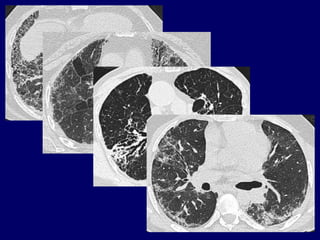

The Many ‘HRCT Faces’ of NSIP

Honeycombing not

a

prominent feature

!!!!

NSIP…

NSIP: initial reports of CT

spectrum of findings:

• Ground glass opacification with or

without areas of consolidation

• Linear opacities and reticular pattern,

but honeycombing limited or absent

• Lower zone predominance, may be

subpleural predilection

Park et al Radiology 1995;195:645

Hartman et al Radiology 2000;217:701

NSIP

A fibrosing lung disease

in which ground glass is

predominant and

honeycombing is minimal

or absent, often with a

peripheral basal

distribution